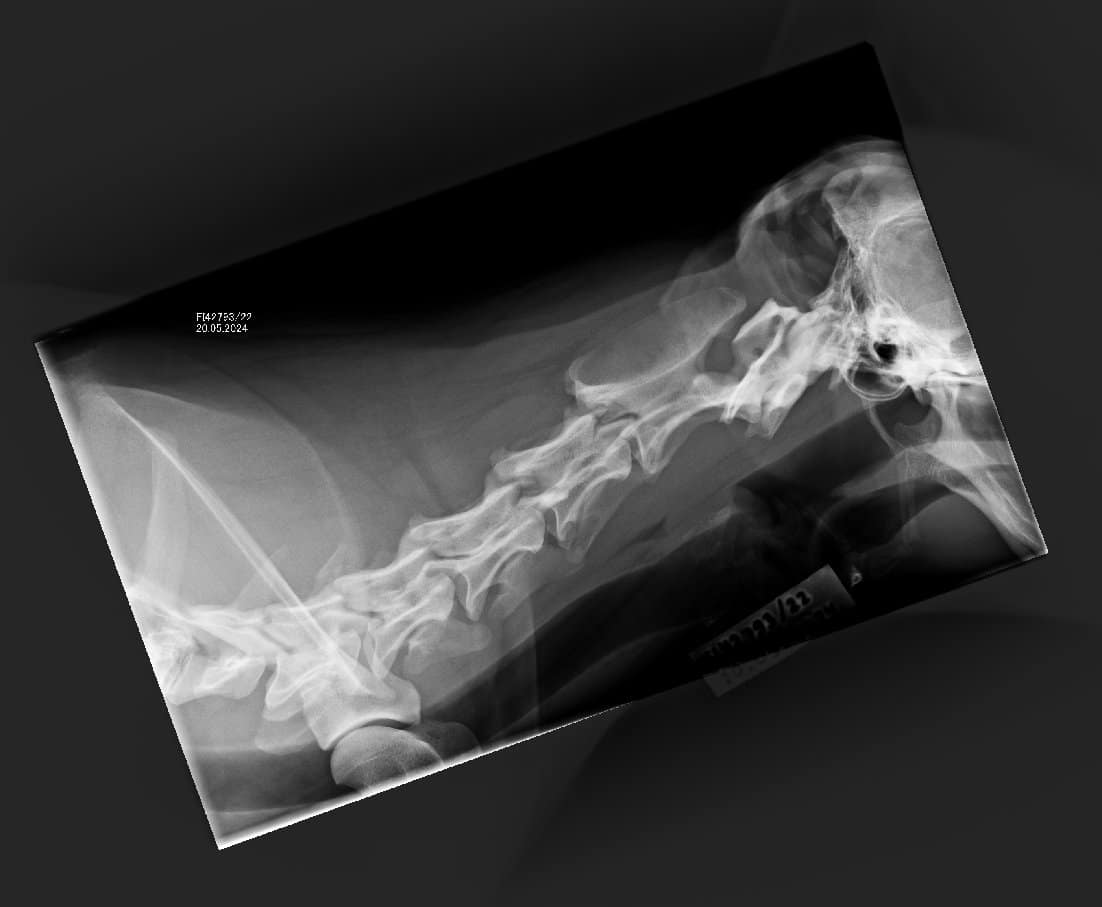

Topin OCD